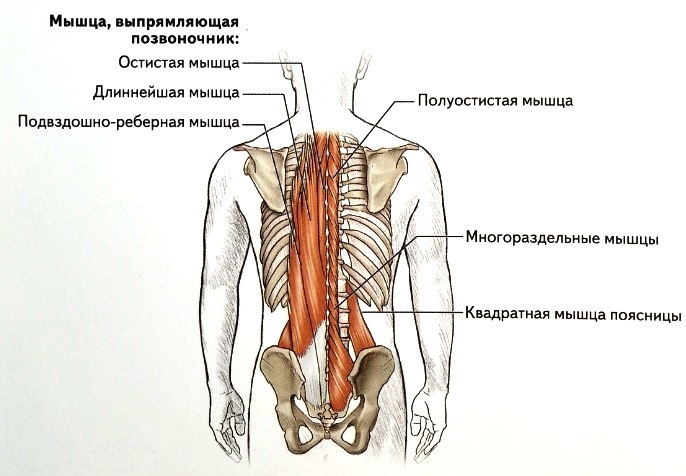

Данные мышцы берут своё начало от задней поверхности крестца, частично от задней части подвздошного гребня и верхней части пояснично-грудной фасции, а затем тянутся вверх делясь на три отдельных мышцы — медиально лежащая остистая мышца, латерально лежащая подвздошно-ребёрная, а между ними пролегает длиннейшая мышца. Все три мышца крепятся по своему ходу к остистым отросткам или рёбрам.

Глубокие мышцы спины представлены тремя слоями. Конкретно вышеперечисленные функции выполняют сразу несколько мышц:

1. Мышца,выпрямляющая позвоночник.Тянется она от крестца до основания черепа,несмотря на то,что в верхней части туловища распадается на три мышечных пучка. Кроме разгибания тела данная мышца выполняет ещё и функцию удержания туловища в вертикальном положении.

2. Поперечно-остистая мышца,составляющая средний слой. Крепится к поперечным и остистым отросткам позвонков,состоит из нескольких пучков,которые совместно тянутся по всей длине позвоночника,выполняет ту же функцию разгибания позвоночника и его вращения.

3. Межостистые мышцы,самый глубокий слой. Расположены между остистыми отростками соседних позвонков почти по всей длине позвоночника,кроме крестца и копчика. Функции всё те же -- разгибание и удерживание позвоночника.

4. Межпоперечные мышцы расположены также по всей длине позвоночника кроме крестца и копчика между поперечными отростками позвонков. Удерживают позвоночный столб в вертикальном положении и наклоняют его.

(Картинки даны последовательно)